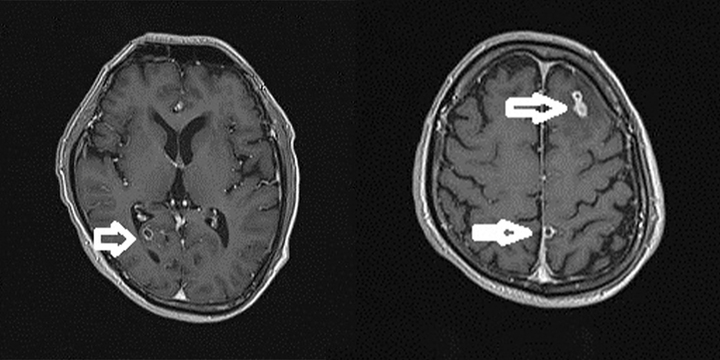

Bệnh viện Hữu nghị Việt Nam - Cuba Đồng Hới vừa tiếp nhận và điều trị cho trường hợp người bệnh bị tổn thương viêm não do nang sán.